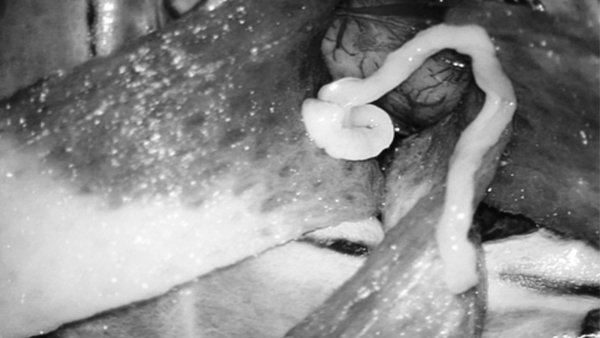

Hình ảnh con sán dây “sống khỏe mạnh” trong não của người đàn ông trẻ.

Ngay lập tức, anh Liu được đưa vào phòng phẫu thuật để loại bỏ ký sinh trùng. Bác sĩ Wang Chunliang, người trực tiếp thực hiện phẫu thuật cho biết khoảnh khắc khi gắp con sán ra khỏi não bệnh nhân, nó vẫn còn sống và ngọ ngậy.

Con sán dây dài 10cm có màu trắng và thân nhỏ như sợi chỉ.